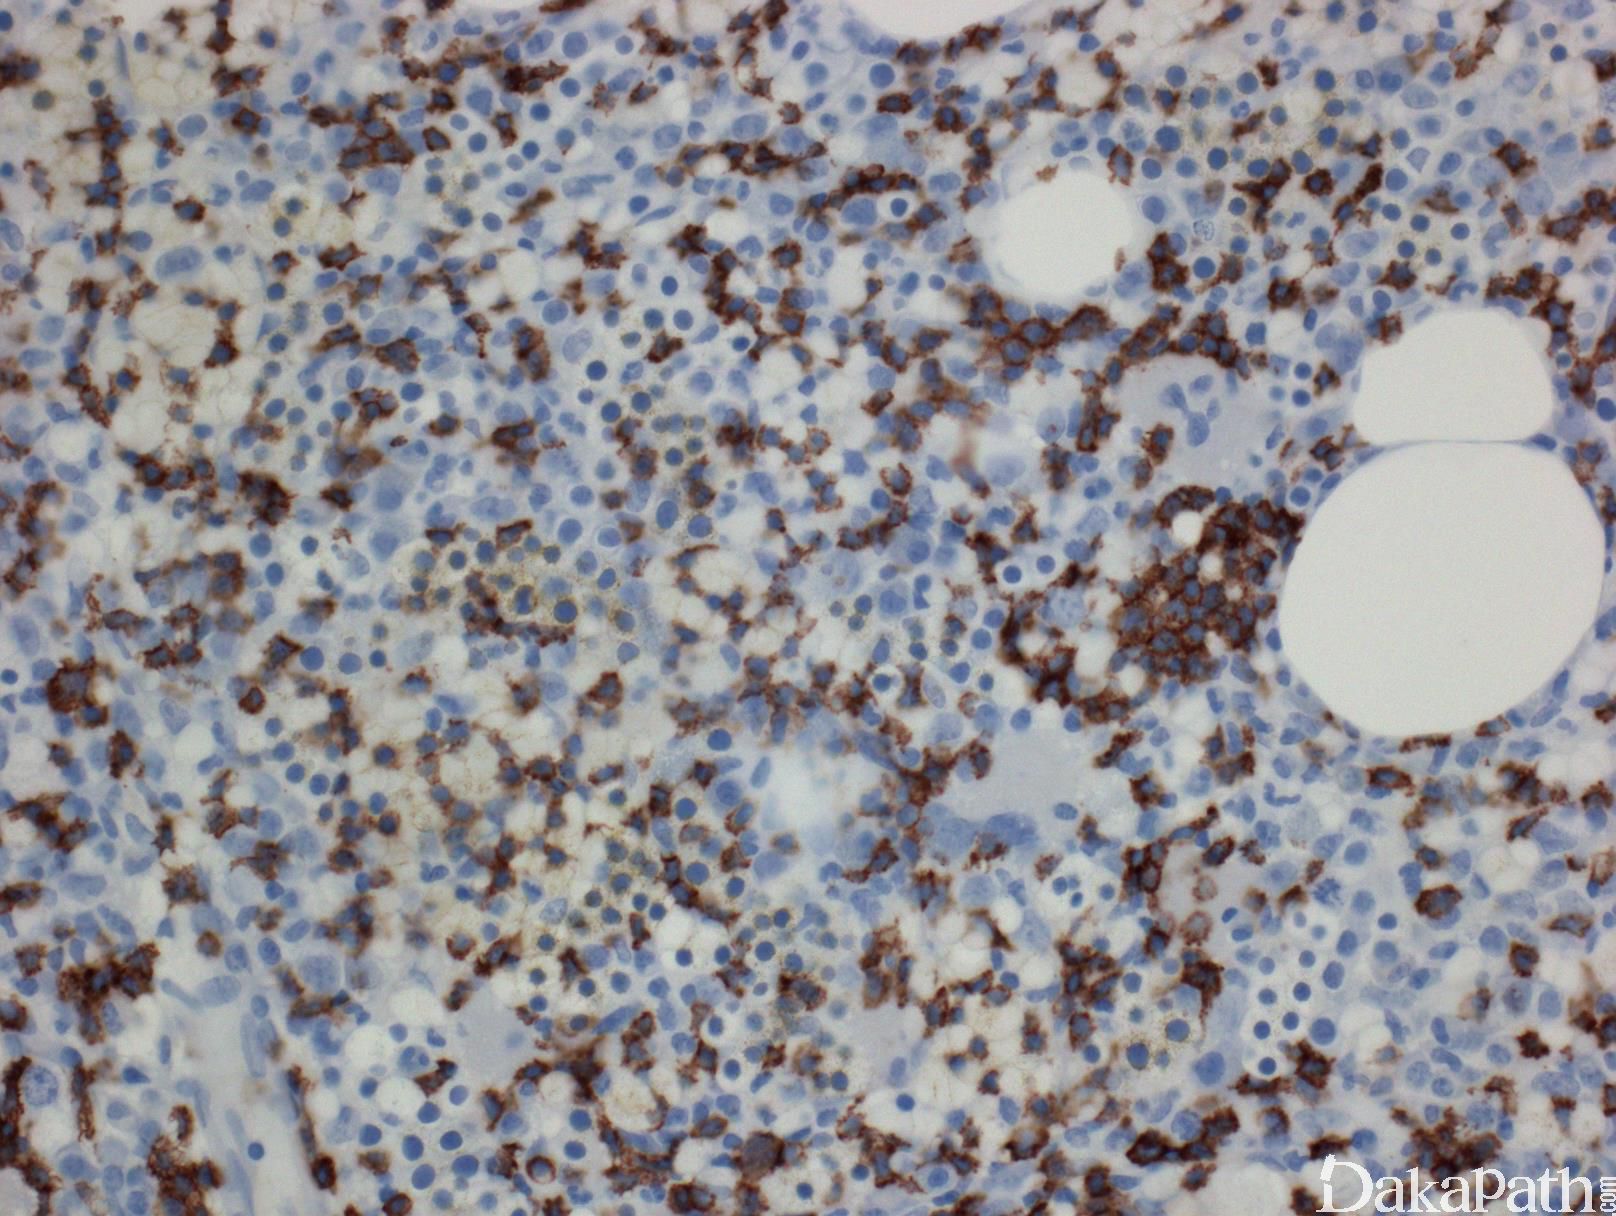

- 骨髓浸润一般为间质,局灶或窦内,常需借助免疫组化才能发现。粒系常轻度左移,红系一般正常,但如并发纯红再障,则红系增生极度低下。

- 免疫表型:典型表型为表面 CD3+、CD2+、CD8+、CD16+、CD57+、TCRα/β(+); 少数病例可表现为 CD4+、TCR α/β+,或 TCRγ/δ+、CD8+、或 TCRCγ/δ+,CD4-、CD8-。 此外,TIA-1+、粒酶 B+、穿孔素+。常见低表达或丢失 CD5 或 CD7。 部分病例表达 KIR 家族受体。 限制性表达 TCRβ 家族谱系或异常表达 KIR 家族谱系可以作为克隆性证据。

免疫组织化学染色:

典型表型为表面 CD3+、CD8+、CD16+、CD57+、TCRα/β(+); 少数病例可表现为 CD4+、TCR α/β+,或 TCRγ/δ+、CD8+,或 TCRγ/δ+,CD4-、CD8-。 此外,TIA-1+、粒酶 B+、穿孔素+。EBER(-)